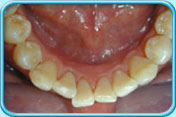

有黑色漬的牙齒經常吸煙或飲用深色的飲品如茶、咖啡等,色素就會沉積在牙齒表面。

清除黑色漬後的牙齒戒煙及減少飲用深色的飲品以減少色素積聚。